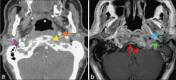

Skull base osteomyelitis (SBO) is a complex and fatal clinical entity that is often misdiagnosed for malignancy. SBO is commonly a direct complication of otogenic, sinogenic, odontogenic, and rhinogenic infections and can present as central, atypical, or pediatric clival SBO. This review describes the clinical profile, investigational approach, and management techniques for these variants. A comprehensive literature review was performed in PubMed, MEDLINE, Research Gate, EMBASE, Wiley Online Library, and various Neurosurgical and Neurology journals with the keywords including: SBO, central or atypical SBO, fungal osteomyelitis, malignant otitis externa, temporal bone osteomyelitis, and clival osteomyelitis. Each manuscript's reference list was reviewed for potentially relevant articles. The search yielded a total of 153 articles. It was found that with early and aggressive culture guided long-term intravenous broad-spectrum antibiotic therapy decreases post-infection complications. In cases of widespread soft tissue involvement, an early aggressive surgical removal of infectious sequestra with preferentially Hyperbaric Oxygen (HBO) therapy is associated with better prognosis of disease, less neurologic sequelae and mortality rate. Complete resolution of the SBO cases may take several months. Since early treatment can improve mortality rates, it is paramount that the reporting radiologists and treating clinicians are aware of the cardinal diagnostic signs to improve clinical outcomes of the disease. It will decrease delayed diagnosis and under treatment of the condition. However, due to rarity of the condition, complete prognostic factors have not fully been analyzed and discussed in the literature.